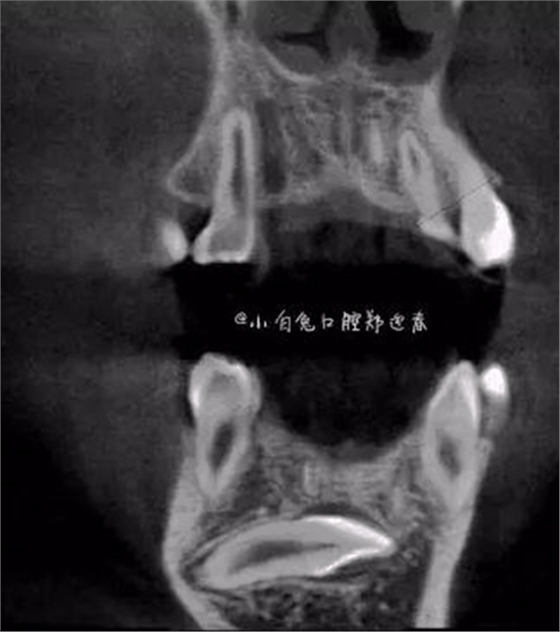

本案:患兒,女,14歲,因牙齒矯正來(lái)院,檢查見(jiàn)83滯留,43未見(jiàn)萌出,拍片發(fā)現(xiàn):43埋伏阻生于31、41、42根尖下方,按照正畸診療計(jì)劃,擬行43拔除術(shù)。

CBCT顯示